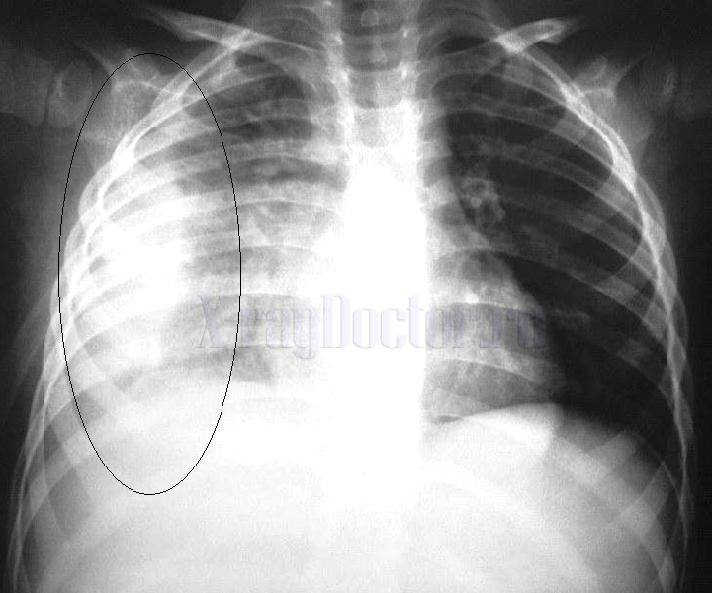

С течением времени в местах отложения фибрина скапливается кальций, поэтому на рентгеновских снимках прослеживаются интенсивные тени. Они не рассасываются и остаются у человека на всю жизнь, а рентгенологи в таких случаях ставят пометку в паспорт регистрации дозовых нагрузок о наличии у человека рентгенопозитивных теней (см. рисунок).

Рентген-картина при патологии представляет собой обширную область затемнения с неровными размытыми контурами, которая постепенно увеличивается в размерах, отражая прогрессирование патологии (см. рентгенограмму).

После излечения гнойного плеврита нередко остаются рубцы или спайки, которые также постоянно будут прослеживаться при выполнении рентгенографии органов грудной клетки.